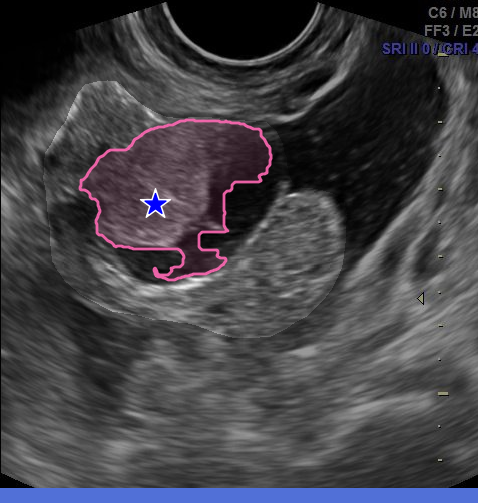

A natural alternative is to mark these extremities directly. The extreme points method [papadopoulos2017extreme] asks annotators to click the top-, bottom-, left-, and right-most points of an instance (Fig. 2ii). This bypasses the need to manually place box corners, as they can be computed automatically, while also providing richer information through four boundary points anchored on the object itself. In their daily practice, clinicians rely on a related but distinct convention: to measure structures in ultrasound, they mark the endpoints of the major and minor axes, a simple gesture that encodes geometry, orientation, and extent (Fig. 2iii). We refer to these as the major/minor points. Both 4-points strategies are fast, intuitive, and better capture instance identity, yet SAM-like models have not been adapted to exploit them.

Major/minor points. We compute a two-component PCA on the border pixels to capture the dominant directions of shape variation (Fig. 4(a)). The first and second principal axes are orthogonal by construction, and each is considered in both directions, giving four directions in total. Border pixels are projected onto these directions (Fig. 4(b)), and candidate points are ranked in each direction based on a score :

where and are normalized projections of along the principal and orthogonal axes, weighted with and . We use and to favor endpoints that are extremal while remaining close to a perpendicular axis, consistent with the axis placement clinicians use in practice. The top- ranked pixels in each direction are then grouped into small top-ranked regions, which are dilated into ROIs (Fig. 4(c)), from which final prompt positions are randomly sampled (Fig. 4(d)). This stochastic sampling keeps prompts near the boundary, slightly inside or outside, capturing realistic annotator variability.